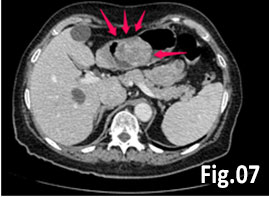

GISTs are rare mesenchymal neoplasms of the digestive tract [1,2]. They have been documented in all parts of the gastrointestinal tract, but are most common in the stomach and small intestine, followed by colo-rectum, mesentery, and esophagus [1,2]. However, the synchronous occurrence of lung cancer and GIST is extremely rare [3]. The incidence of GIST coexisting with additional malignancies is 9% to 27%, and primary lung cancer in GIST patients is 0.5%-1.2% [3]. A 75 year old woman with a smoking history for >30 years was diagnosed with advanced stage of left lung primary adenocarcinoma by chest computed tomography (CT) and bronchoscopy with sampling in February 2015 (Fig.1, Fig.2). The patient started Erlotinib 150 mg/day. In September 2015 the patient was admitted with vague abdominal pain and postprandial vomiting. Physical examination, routine blood, urine and stool investigations were unremarkable. Abdominal ultrasound detected an oval, homogenous, hypoechoic lesion 6/5/4 cm, arising from the submucosal layers of the gastric wall (Fig 3). The color Doppler demonstrated neovascularization (Fig 4). Except for 3 small simple liver cysts, no other abnormalities were present. Upper endoscopy and endoscopic ultrasound (EUS) revealed a large oval, slightly lobulated mass, hypoechoic 6x5cm between incisura angulars and greater curvature of the gastric body, originating from the 4th layer of the wall (muscularis propria). The tumor was slightly “dumbbell” shaped, protruding in and outside the stomach lumen, with several irregular hypoechoic zones and micro cysts within, looked encapsulated without infiltration of the surrounding tissues and pathologic abdominal lymph nodes (Fig. 5). A contrast-enhanced ulstrasound (CEUS) and contrast-enhanced computed tomography (CECT) of the abdomen additionally characterized the lesion and excluded liver metastases. (Fig. 6, Fig. 7) Percutaneous true-cut biopsy of the lesion was performed (18G, two separate puncture sites) (Fig 8). The immunohistochemical analysis revealed epithelioid-type GIST, diffusely positive for c-kit (CD117), with a weak focal expression of S-100 (Fig. 9). Due to life expectancy defined by the unresectable advanced lung cancer, the patient was not indicated for resection of the gastric GIST. Imatinib (Glivec) 400 mg/day was started as a “co-therapy” to Erlotinib in November 2015. After 12 months of co-treatment, a good control of both tumors was achieved. CT and abdominal ultrasound showed the gastric lesion was slightly shrunk on therapy, with large central necrosis (Fig. 10). The patient is being followed up.

Figure 7. CT(CECT): Hyperenhanced tumor with heterogeneous structure, sized 68х57x45 mm, probably GIST. No significant lymph nodes or secondary lesions. Small simple liver cysts.